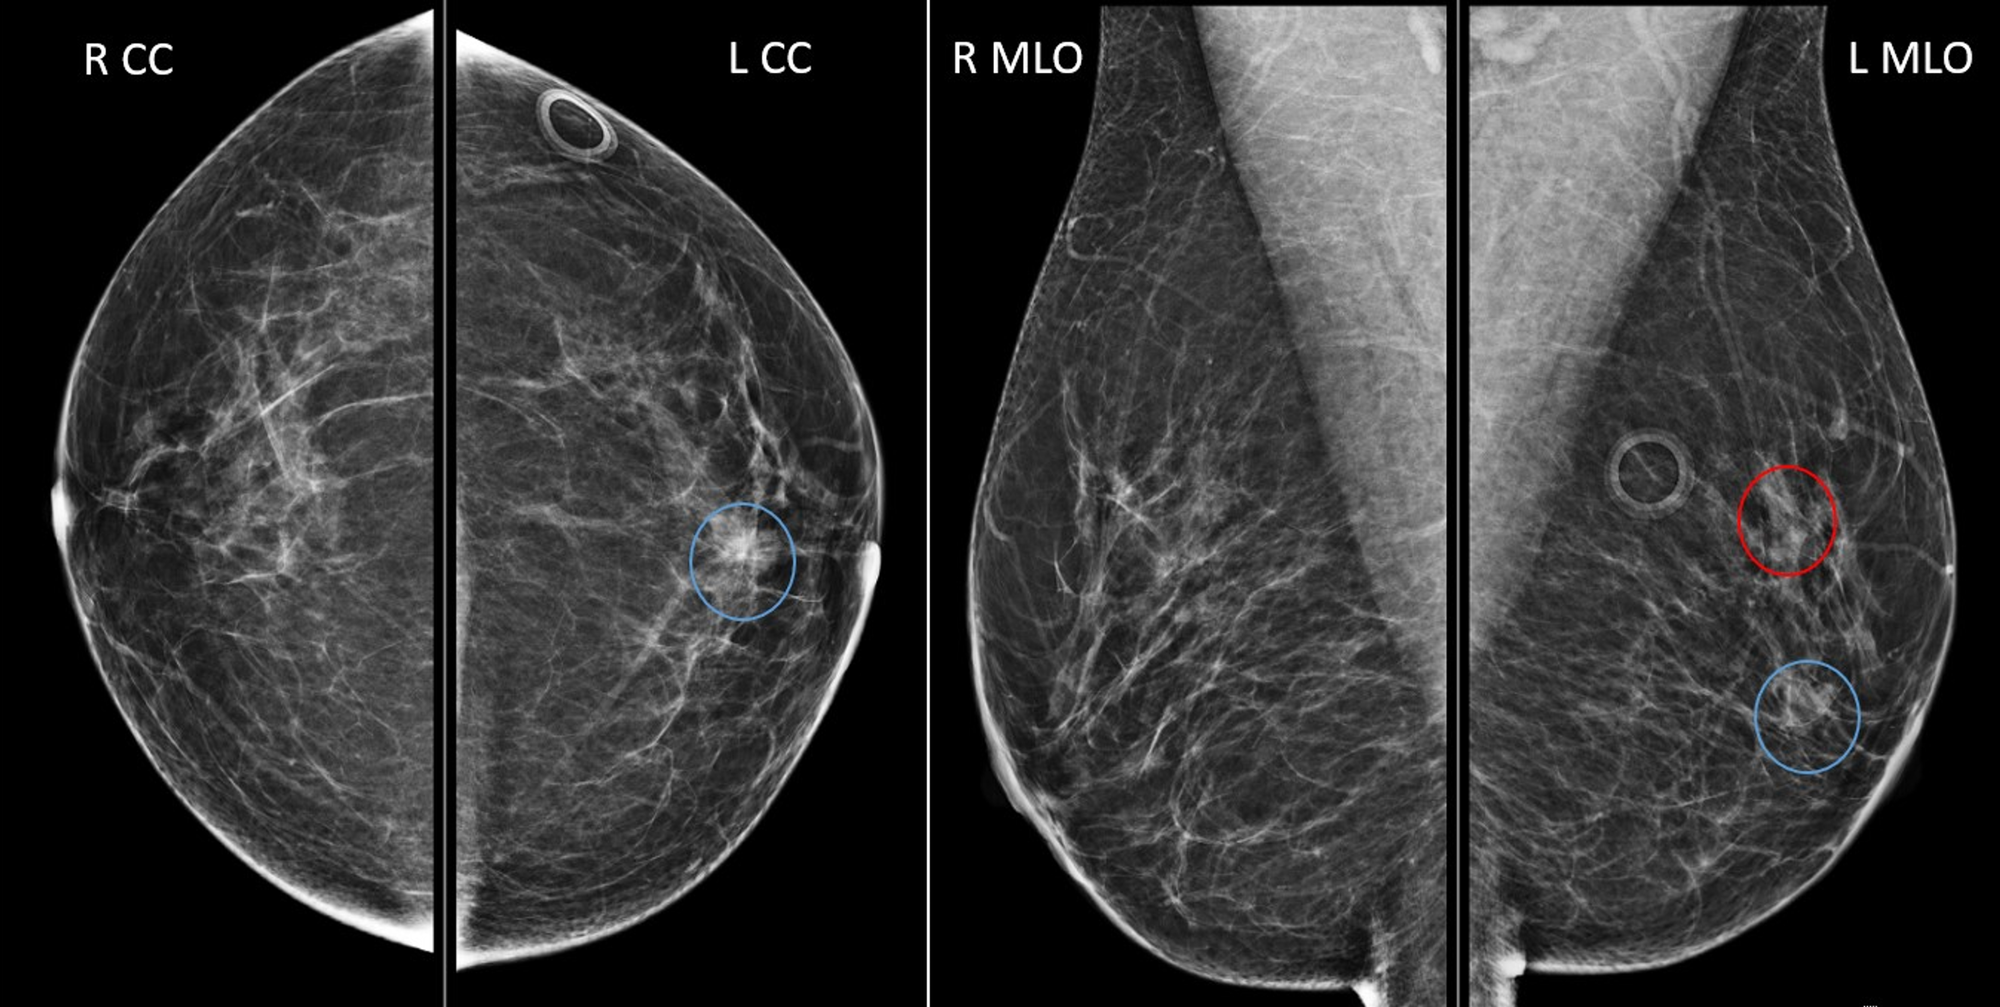

A 31yearold female came followup after right breast lumpectomy. a CC Screening Or Diagnostic Mammogram After Lumpectomy among 707 women who were recommended to undergo annual diagnostic mammography (dm) surveillance after lumpectomy for. “after a lumpectomy, your mammogram screenings will take place as usual. among 707 women who were recommended to undergo annual diagnostic mammography (dm) surveillance after. you may still need mammograms and other breast cancer screening after lumpectomy, mastectomy, or breast. Screening Or Diagnostic Mammogram After Lumpectomy.